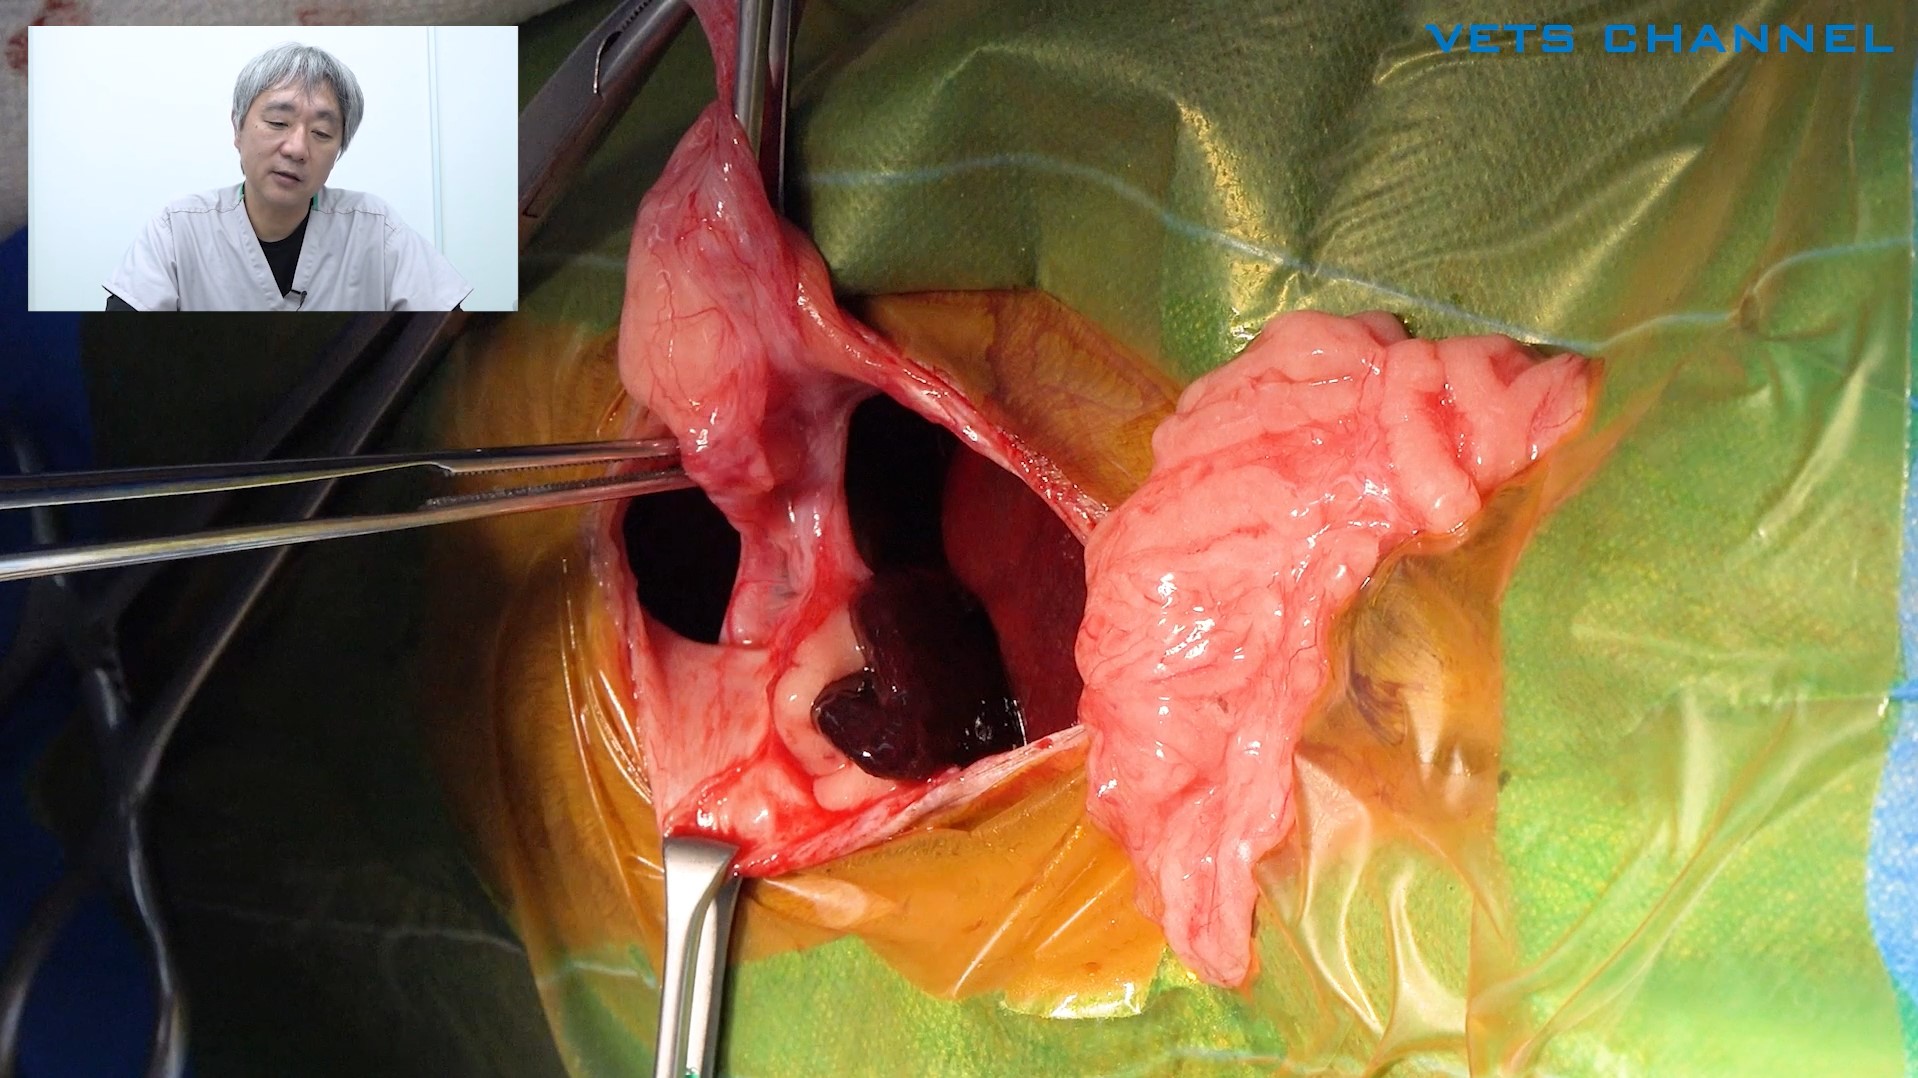

腫瘍に対する腸管切除および吻合術

- OPE

- 軟部外科

- 消化器科

- 猫

上原 拓也先生(小滝橋動物病院 目白通り高度医療センター)

59分

2025/10/31

腫瘍に対する腸管切除および吻合術

- OPE

- 軟部外科

- 消化器科

- 猫

上原 拓也先生(小滝橋動物病院 目白通り高度医療センター)

59分

2025/10/31